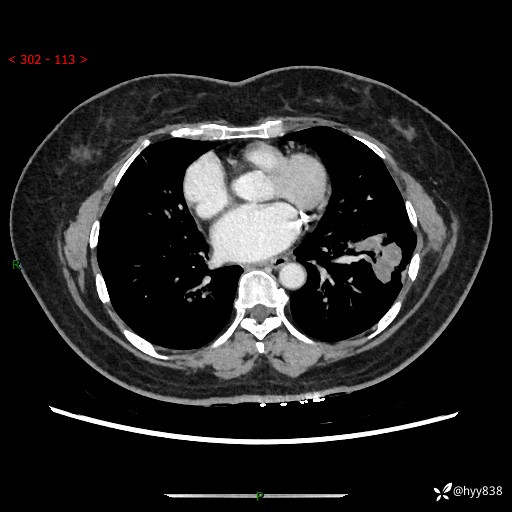

【现病史及既往史】:患者自诉2月前体检发现肺结节(左肺下叶约17mm,右肺上叶4mm),未予特殊处理,2024-10-12当地市第五医院门诊复查胸部CT提示右下肺结节(大小约3.3cm*3.9cm),患者无咳嗽、咳痰,无畏寒、发热、盗汗,无咯血,无胸闷、胸痛、呼吸困难,无恶心、呕吐,无腹痛、腹胀、腹泻等不适,现为求进一步诊治,门诊以“孤立性肺结节”收住我科。 患者本次起病来精神、食欲、睡眠尚可,大小便正常,体力、体重无明显变化。

【检查】:胸部CT增强检查